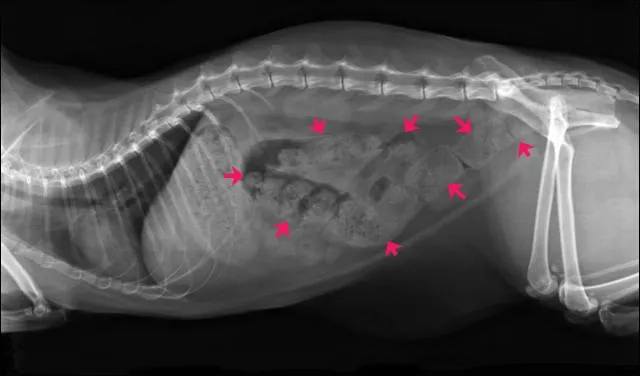

下图片子中,红色箭头部分,都是未排除的屎: